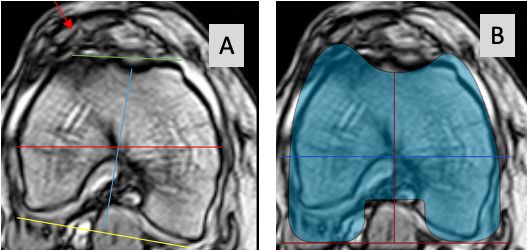

Some surgeons recommend to routinely perform 3-D analysis before surgery, and this is mandatory for surgeons using patient specific cutting blocks and robotic surgery. This 3-D planning allows not only to identify any axial plane deformity of the femur and tibia before surgery but also makes proper correction during surgery easier and more reproducible. We do not routinely plan the axial plane with CT or MR imaging. History, clinical examination and axial weight bearing patella views are routinely used to identify any patella maltracking or asymmetric flexion gap. Only in cases with complex patella dislocations, we perform a rotational profile with MR imaging, to identify where the axial plane deformity is located (femur, tibia or both) (Fig 14).

On standardized AP and lateral radiographs these axial plane deformities cannot be identified. The golden standard for the identification of proximal tibia axial plane deformities is still CT or MRI imaging (Fig 23 A and B) [5,30].

Some surgeons recommend to routinely perform 3-D analysis before surgery, which allows not only to identify any axial plane deformity of the femur and tibia before surgery but also makes proper correction during surgery easier and more reproducible [7]. We do not routinely plan the axial plane with CT or MR imaging. Only in cases with complex patella dislocations, we perform a rotational profile of the knee with MR imaging, to identify where the axial plane deformity is located (distal femur, proximal tibia or both) (Fig 14).